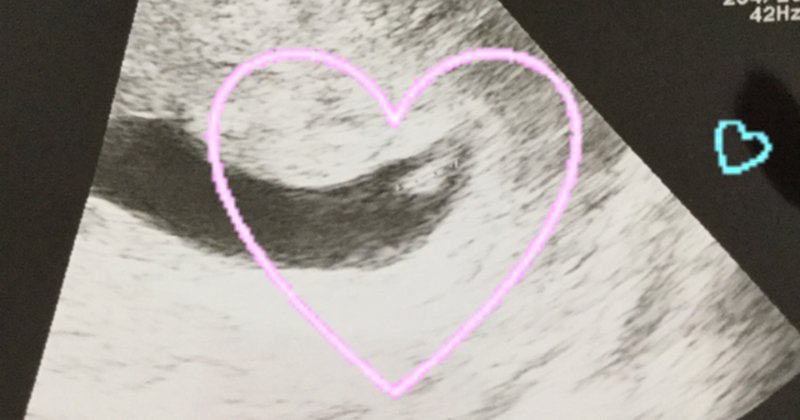

★6週(6W1D) 心拍確認 胎嚢(GS)55cm 胎芽13mm 心拍数1bpm 我が家にとって、初めての心拍確認。うれしかった。とりあえず一安心するとともに、まだまだ不安でいっぱい。標準的な値だということ。ちなみに、ここからは、βhCGは測っていない。「 この時期に心拍が視認できるのはとてもよいです! 」 というわけで、はからずも 6w1d、心拍が確認できました! 小さな小さな胎芽がペコペコ動いているのが見えました。 本当に神秘的で、その瞬間、胸がいっぱいになったのを覚えています。

6w1d心拍確認できた! よく見るのはチカチカ動いてる♡みたいなやつだけどわたしはあんまりわからなかった。 心拍確認できたことにより、母子手帳の受け取り指示がありその日のうちに近くの出張所で受け取りできました。 わたしの区は結構あっさり5w1d⇢⇢6w1d 胎嚢 8mm⇢⇢⇢24mm 胎芽 なし ⇢⇢⇢ 2mm 標準とかわかりませんが、 先生から順調だと言われたので その言葉を信じたいと思います\ (^^)/ 心拍が見られただけ嬉しい\ (^^)/ IVFなんばでは、 4wと5wは筋肉注射がありますが